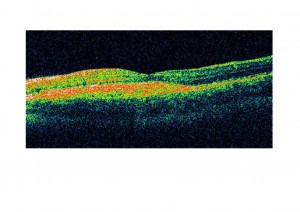

La anomalía se localiza en el cromosoma 11q13 y el gen causal es VMD2, que codifica la bestrofina, una proteína de los canales del cloro, que se localiza en la membrana plasmática de las células del epitelio pigmentario. Se cree que un transporte anómalo del cloro, motivado por las mutaciones en este gen podría alterar el transporte de líquido a través del epitelio pigmentario de la retina provocando un acúmulo de restos entre el epitelio pigmentario y los fotorreceptores de la retina y entre el epitelio pigmentario de la retina y la membrana de Bruch (como aparece en las OCT de un niño afectado de dicha enfermedad atendido en nuestra consulta).